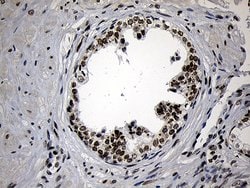

ZNF670 Monoclonal Antibody for Western Blot, IHC (P)

| Immunohistochemistry (Paraffin), Western Blot | |